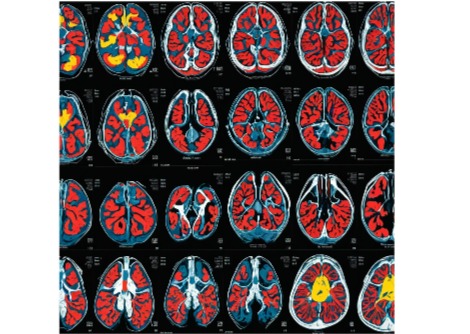

فحص خلايا الأسنان على جهاز كمبيوتر أثناء البحث في زراعة بدائل من الخلايا الجذعية.